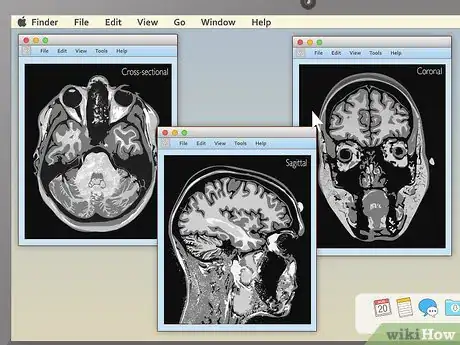

1Familiarize yourself with the different MRI viewing schemes. When your MRI first loads up, if you're lucky, it will be immediately obvious what you're looking at. However, in many cases, the image you see may be a completely unintelligible mix of black, white, and grey. Knowing how MRIs are shot can help you make sense of your images. The three main ways MRIs are displayed are:[4]

- Sagittal: Often the easiest for non-doctors to interpret. Sagittal MRIs are basically side or profile views of your body. The image is as if you've been sliced in half vertically, from your head to your pelvis.

- Coronal: These images are basically a "head on" view of your body. You're looking at your features vertically from the front — as if you were standing facing the camera.

- Cross-sectional: Often the hardest for non-doctors to interpret. Here, you're basically viewing thin slices of your body from the top down — as if you've been cut into many thin horizontal slices from your head to your toes like a salami.

3Pick an appealing series layout. MRI programs almost always have the ability to display more than one image at once. This makes it convenient for doctors to compare different views of the same area or even MRIs taken at different times. For most non-doctors, it's easiest to simply choose a one-image-at-a-time layout and cycle through the images individually. However, there should be onscreen instructions to show two, four, or many more images at once, so feel free to play around with this feature.